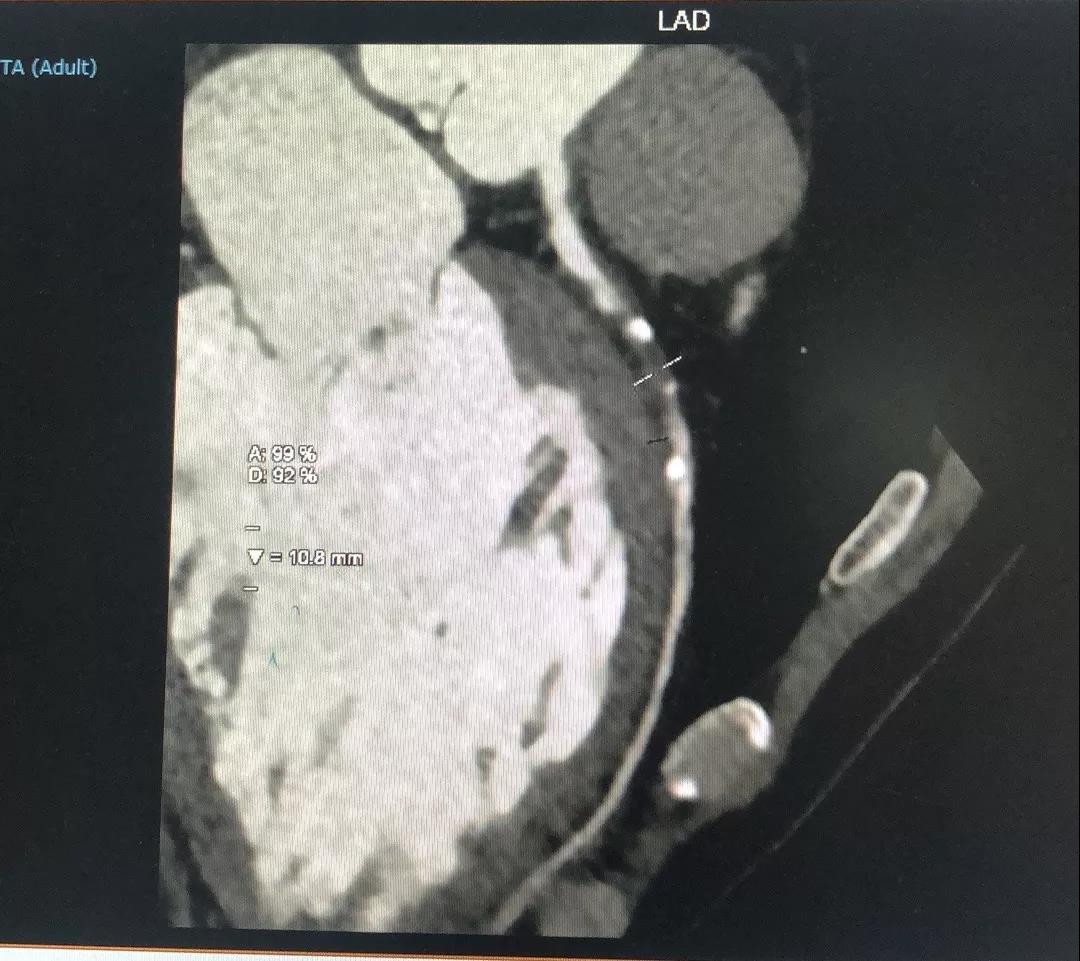

四、冠状动脉CT(CCTA)

关于LAD

LAD CTA特点:

1、LAD发出第二对角支后即慢性闭塞;

2、闭塞入口不太清楚;

3、闭塞近段存在内膜钙化;

4、闭塞段血管的走行相对较直;

5、闭塞出口相对“健康”;

关于RCA

RCA CTA特点

1、入口清楚;

2、闭塞段长度小于20cm;

3、闭塞段血管无明显扭曲;

4、闭塞段内有两处明显的钙化斑块;

5、闭塞出口处血管相对比较“健康”;

6、侧枝血管汇入左室后支;

7、后三叉处的血管相对比较“健康”。